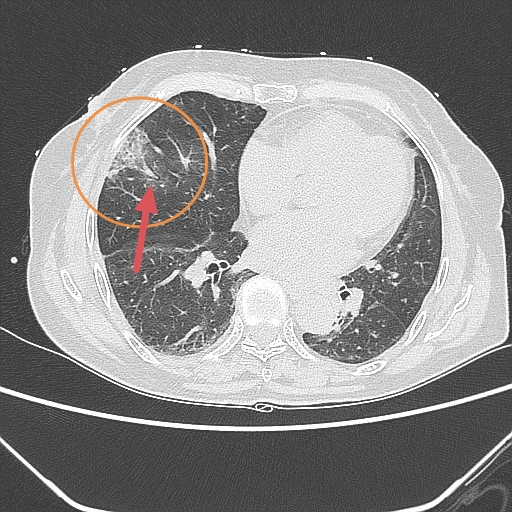

肺部有阴影是什么病症?

肺部疾病常常会在CT影像中显示出阴影,最常见的是肺部感染性疾病,如肺炎,包括大叶性和小叶性肺炎,还有结核病灶当然,肺癌也有可能导致肺部阴影的出现若影像学检查无法明确诊断,医生可能会建议进行进一步的检查,如肺部纤维支气...